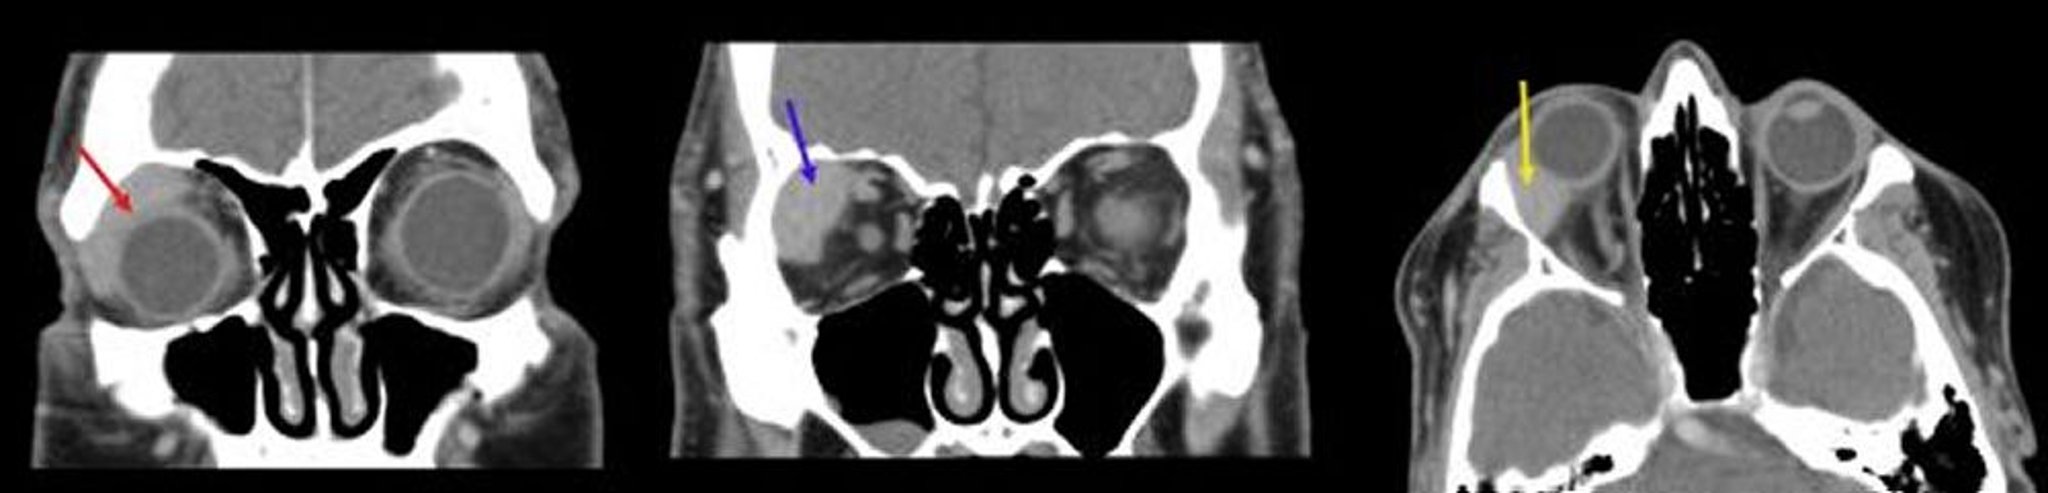

Linfoma orbitario

En esta imagen, la primera TC coronal (izquierda) muestra una masa homogénea que se ajusta al globo (flecha roja). La segunda TC coronal (centro) muestra una masa bien delimitada en la fosa de la glándula lagrimal derecha (flecha azul). La TC axial (derecha) muestra una masa homogénea en la fosa lagrimal co la forma del globo ocular derecho (flecha amarilla).

Images courtesy of James Garrity, MD.